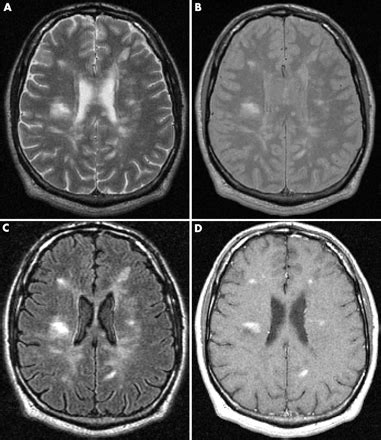

Imaging in multiple sclerosis | Journal of Neur...

Multiple sclerosis | Radiology Reference Articl...